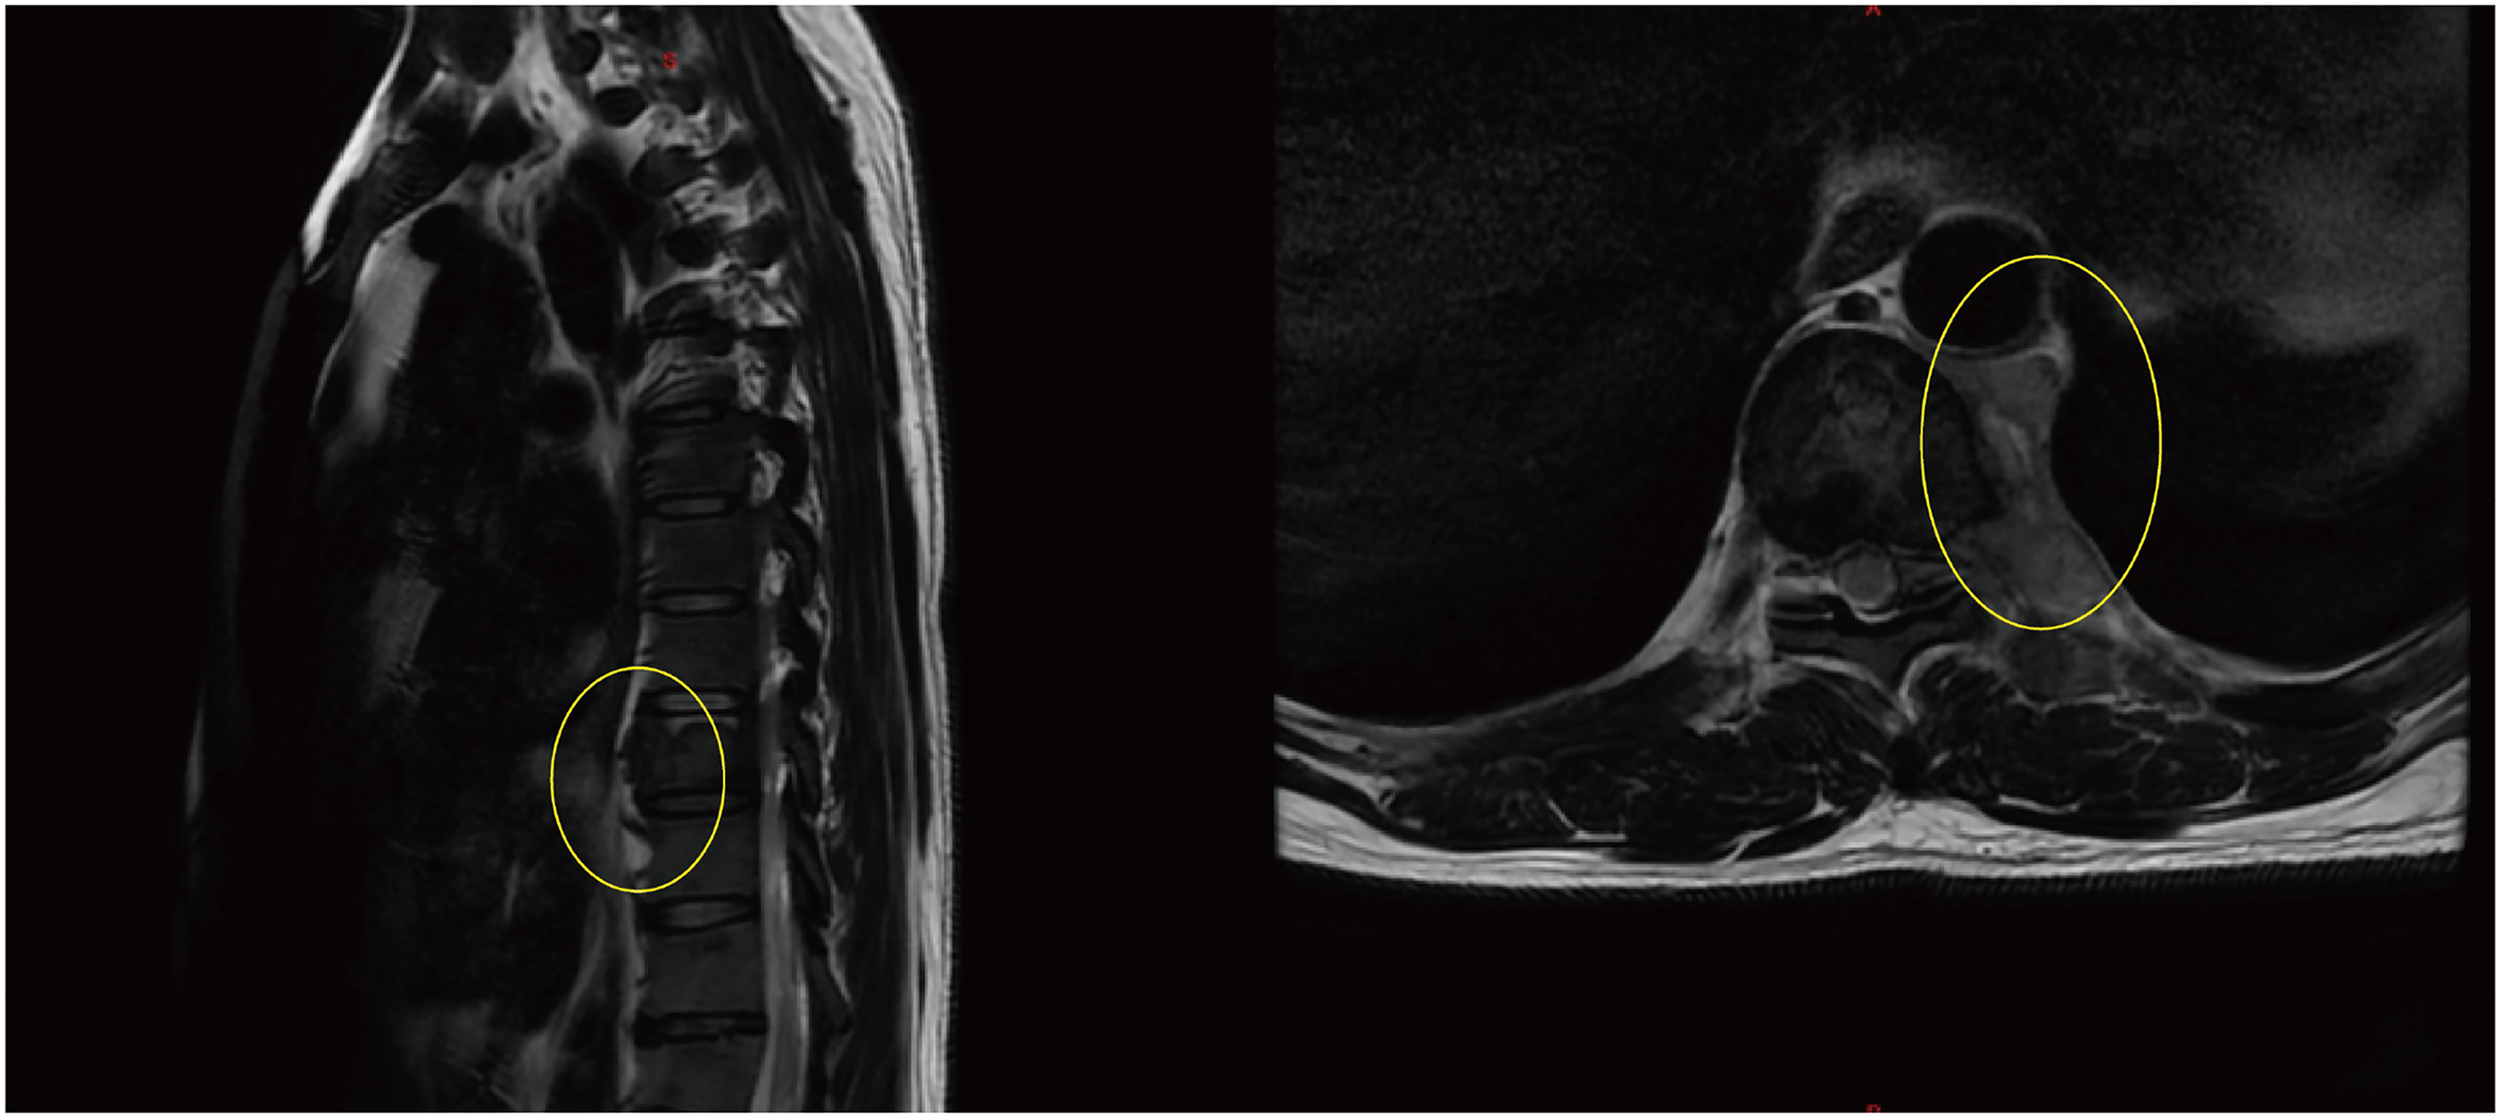

Background Acute promyelocytic leukemia (APL) caused by the TTMV::RARA fusion gene is extremely rare, with fewer than 10 formally reported cases worldwide, and routine molecular tests often fail to detect it. This case is unique because the disease first manifested as vertebral myeloid sarcoma. Although bone marrow morphology and immunophenotyping strongly suggested APL, routine diagnostic methods could not confirm the disease, and the final diagnosis relied on whole- transcriptome sequencing. Case Summary A 39- year- old man was admitted for persistent lower back pain and limited movement of the left lower limb. Imaging revealed destruction of the T9 vertebral body with paravertebral and mediastinal soft- tissue masses. Pathology of the resected mass confirmed myeloid sarcoma. The patient developed pancytopenia and coagulopathy. Bone marrow morphology and flow cytometry showed classic features of APL, and all- trans retinoic acid (ATRA) induction therapy was initiated. However, PML:: RARA PCR and RARa FISH were negative, fusion gene screening and karyotyping found no abnormalities, and the diagnosis was revised to AML, prompting a switch to IA chemotherapy. As the diagnosis remained unclear, whole- transcriptome sequencing was performed and revealed a TTMV::RARA fusion, which was confirmed by RT- PCR. The patient was ultimately diagnosed with TTMV::RARA APL. He later discontinued treatment and died months afterward. Conclusion This report presents a rare adult case of TTMV::RARA acute promyelocytic leukemia presenting as vertebral myeloid sarcoma. Whole-transcriptome sequencing was essential for diagnosis after routine molecular tests were negative, highlighting the importance of considering rare RARA fusions in APL-like cases lacking PML::RARA. TTMV::RARA APL may be sensitive to ATRA/ATO-based therapy; however, the patient discontinued treatment. Further cases and clinical experience are needed to optimize management strategies for this rare APL subtype.